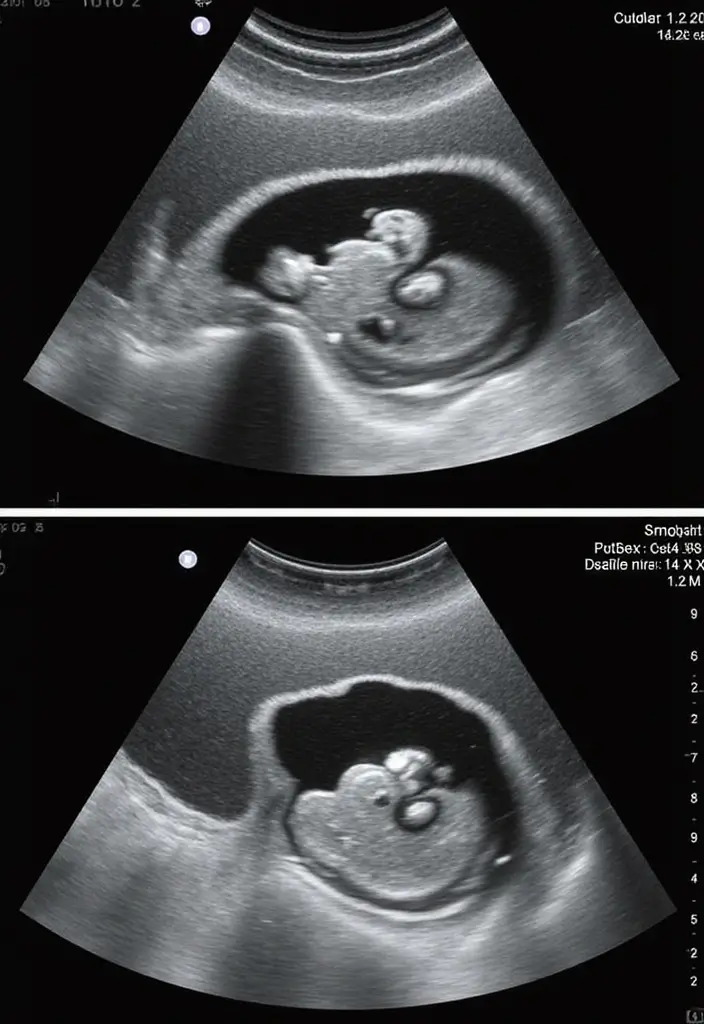

If you’re pregnant, you want a clear read on your baby’s health. Nuchal translucency is a small space at the back of the neck seen on an ultrasound. It is filled with fluid.

You’ll usually see it in the first trimester, around weeks 11 to 14. A thicker NT can mean a higher chance of chromosomal issues, such as Down syndrome, or other conditions. Still, a larger NT does not confirm a problem. It simply flags a need for more checks.

How the test works: NT is measured during a routine ultrasound. It is non-invasive and is often paired with a blood test. Together, they give a better risk estimate and help you decide what comes next.

– NT is measured in millimeters. Typical values are about 1.0 to 2.5 mm, but this can vary.

Nuchal Translucency (NT) refers to a small pocket of fluid found at the back of your baby’s neck during an ultrasound, typically between 11 to 14 weeks of pregnancy. This measurement is crucial as it helps assess the risk of certain chromosomal abnormalities, such as Down syndrome. An increased NT measurement may indicate a higher risk, prompting further testing to provide clearer insights into your baby’s health.

What Should I Expect During the Nuchal Translucency Screening?

During the NT screening, you can expect a non-invasive ultrasound that measures the fluid at the back of your baby’s neck. It’s a quick process, usually taking about 15-20 minutes. The technician will guide you through the procedure and answer any questions you might have. Remember, this test is a screening, not a definitive diagnosis, and results will be explained to you afterward, helping you understand your risk factors.